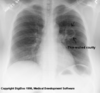

What is this CXR showing?

* RML pneumonia * You can rule out RLL pneumonia because there is no accumulation at the base of the lung. * A lateral CXR will have the best view for confirmation.